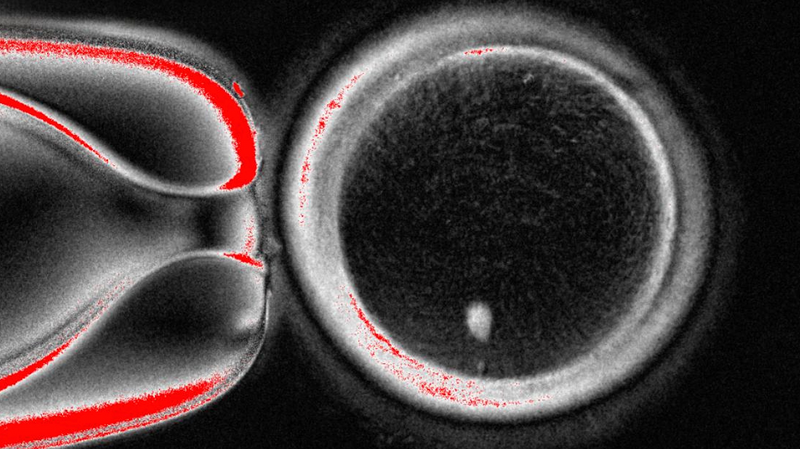

Picture this: scientists have found a way to transform human skin cells into functional eggs in a lab. 🥚🔬 It's a bold move that could change the game for infertility! Researchers removed the nucleus from a skin cell and inserted it into an egg cell stripped of its own nucleus. This new trick, named mitomeiosis, mimics nature’s way of discarding extra chromosomes, leaving behind a perfect set of 23 for healthy development.

So far, researchers fertilized 82 of these lab-made eggs with sperm. About 9% grew into blastocysts (those 70–200 cell embryos used in IVF), but none advanced past that stage. Most stopped at 4–8 cells or showed chromosome glitches. 🚧